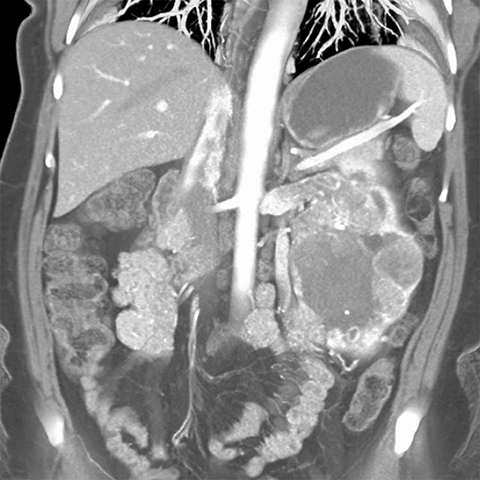

67-year-old male with flank mass and hematuria [2 of 4]